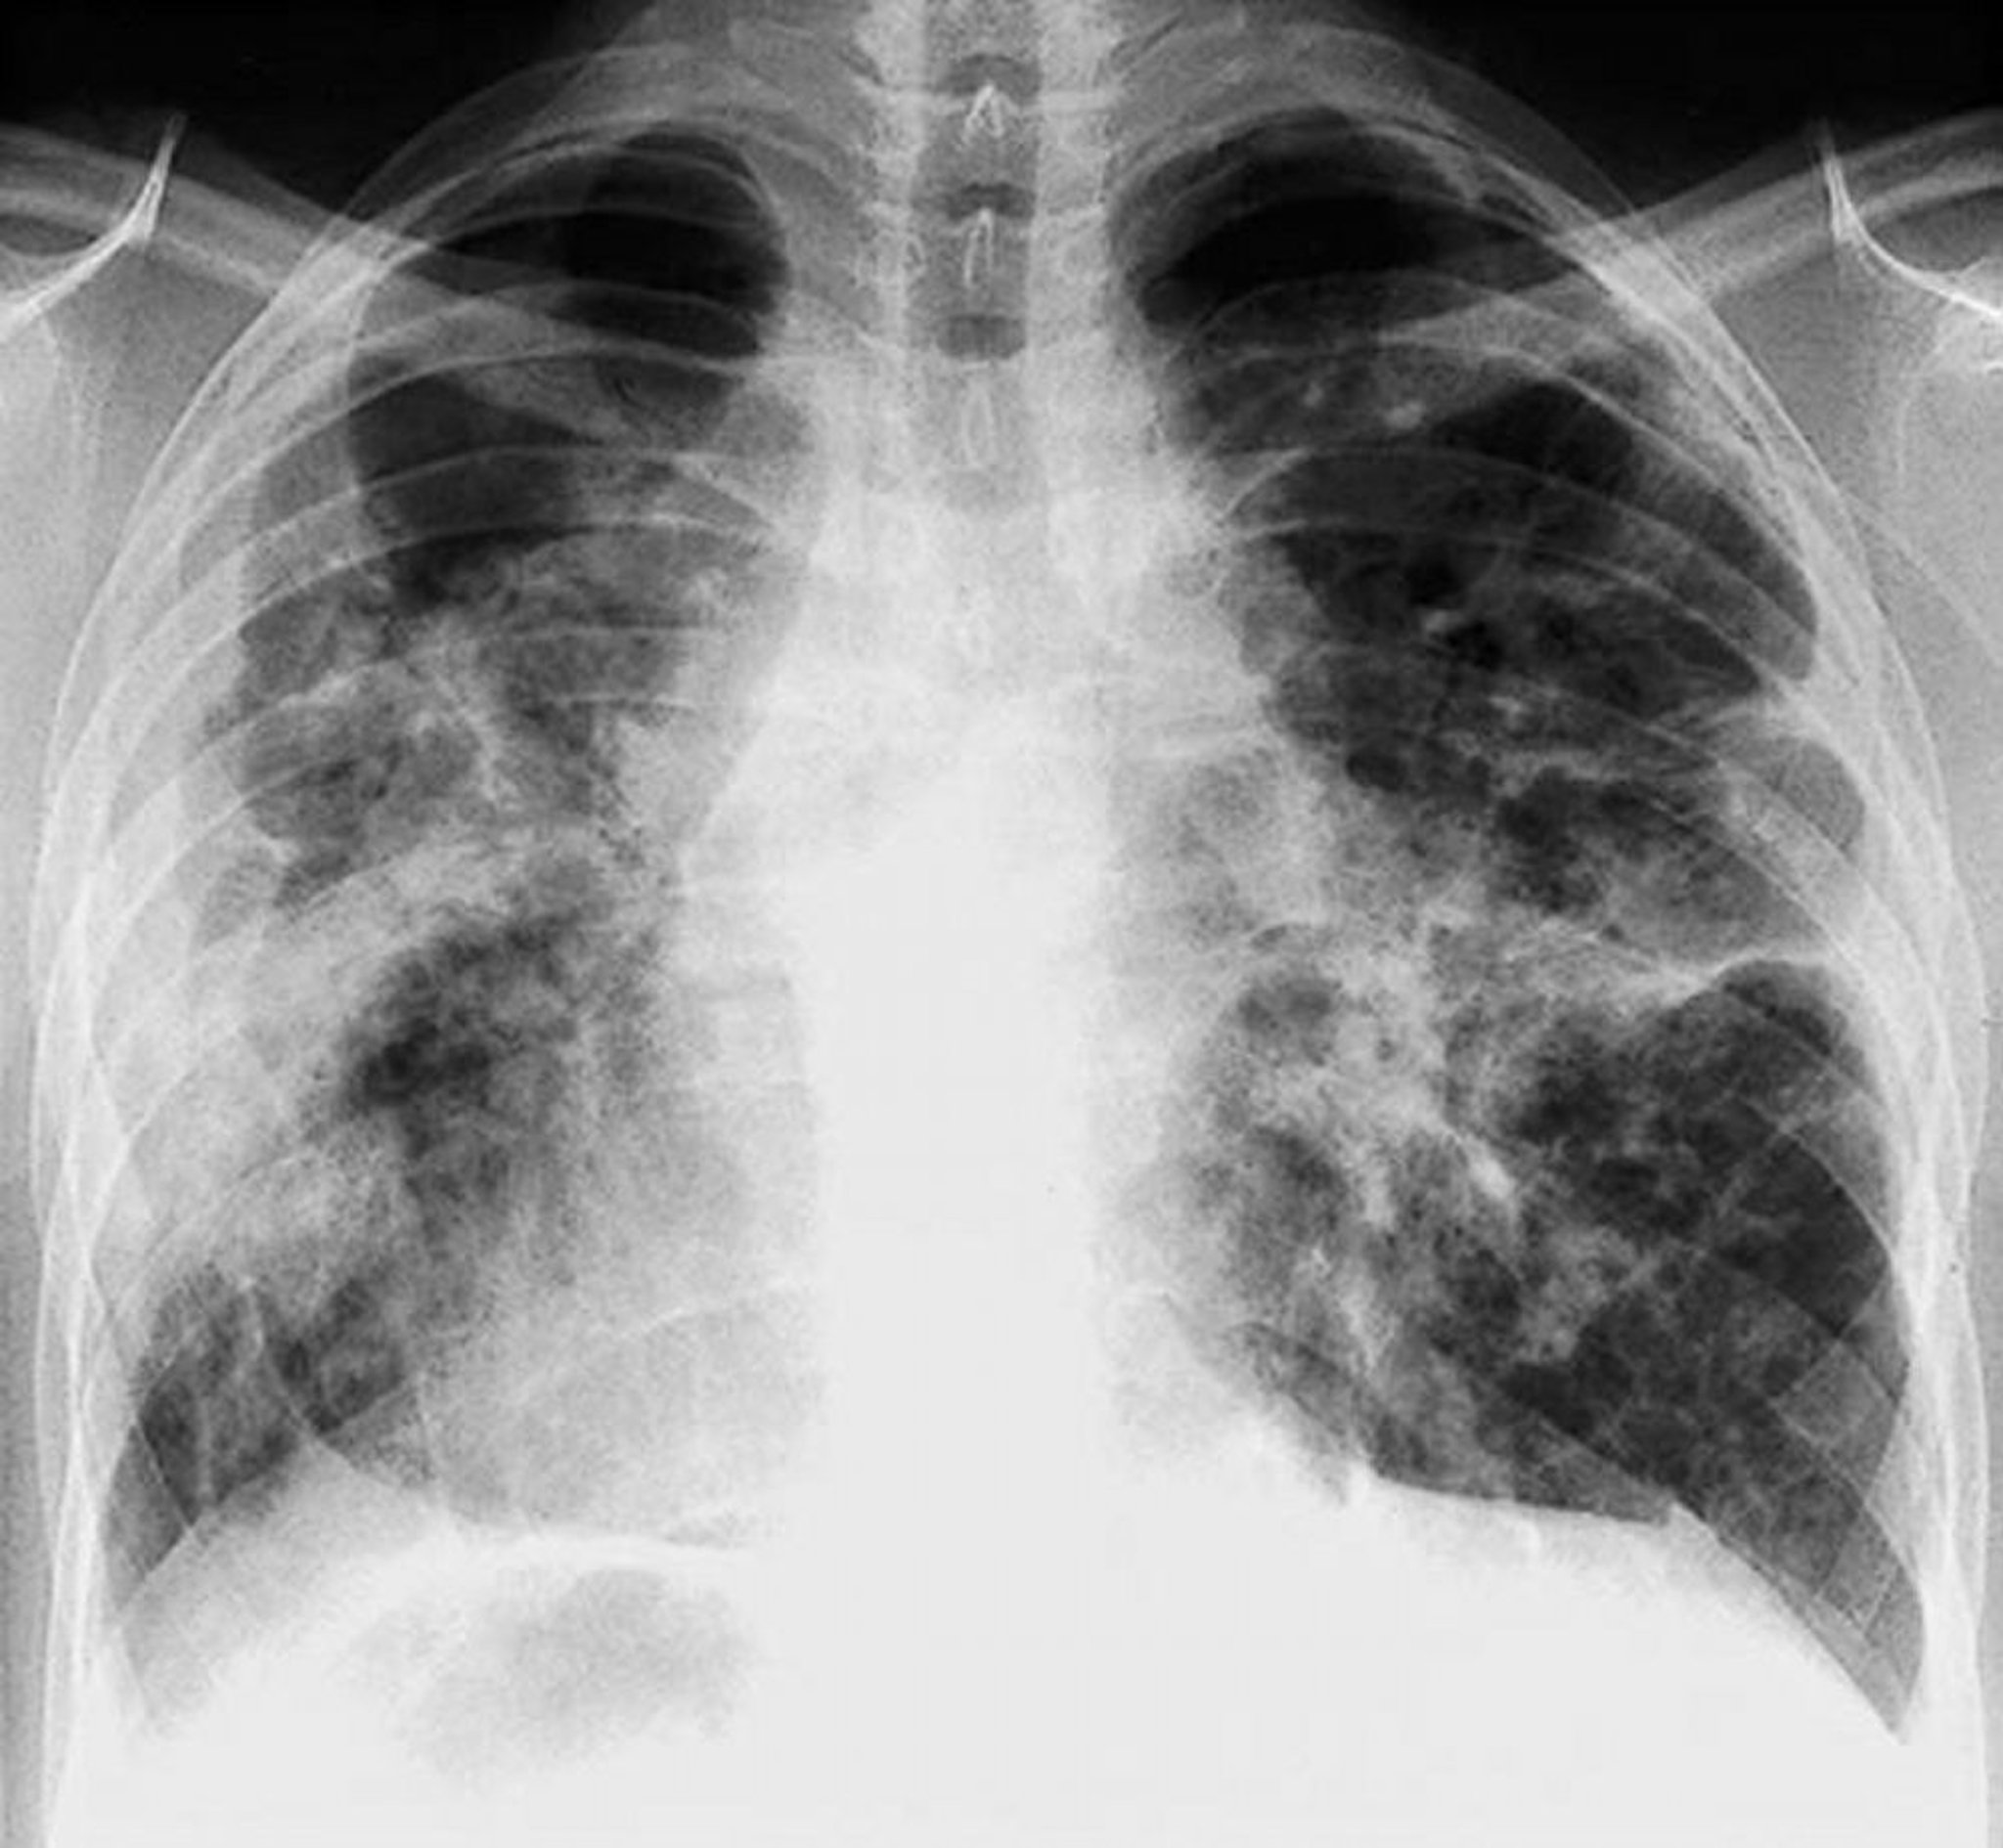

Sarcoïdose (stade IV)

Fibrose sévère, diffuse avec adénopathie hilaire et anomalies kystiques des lobes supérieurs au stade IV de la sarcoïdose.

By permission of the publisher. From: Tanoue L, Elias J. In Bone's Atlas of Pulmonary and Critical Care Medicine. Edited by J Crapo. Philadelphia, Current Medicine, 2005.